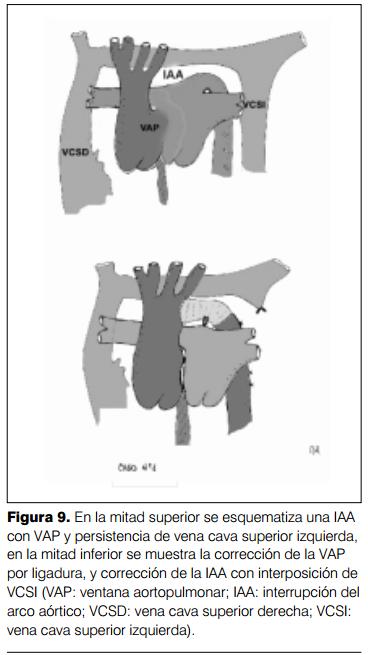

Cirugía: paciente en decúbito lateral derecho, apertura del tórax en cuarto espacio intercostal izquierdo. Se comprueba interrupción del arco aórtico luego del nacimiento en ramillete de los vasos del cuello, aorta descendente de buen calibre, alimentada por grueso ductus. Doble vena cava superior, sin la presencia de tronco innominado. Apertura del pericardio prefrénico. Disección e interrupción de ventana aortopulmonar por doble ligadura, optándose por este procedimiento debido a las malas condiciones generales del paciente. Mejoría ostensible de la hemodinamia comprometida hasta ese momento. Disección de la aorta ascendente, vasos de cuello y aorta descendente, ligadura, sección de grueso ductus y resección del tejido ductal remanente en el cabo aórtico distal. Resección de un segmento de vena cava superior izquierda que se utiliza para restablecer la continuidad del arco aórtico, entre el nacimiento de las arterias carótida y subclavia izquierdas y la aorta torácica descendente.

La acción quirúrgica sobre la VAP implica ligadura de la misma (con riesgo futuro de estenosis en el tronco de la arteria pulmonar) o sección, con cierre directo de la aortotomía y cierre del tronco de la arteria pulmonar mediante parche. La táctica quirúrgica sobre la IAA consiste en la anastomosis término terminal de la aorta si se logra una adecuada movilización de los cabos aórticos proximal y distal. Si ello no es posible, se deberá recurrir a la reconstrucción del arco aórtico con un homoinjerto vascular o con material protésico, que implica estenosis relacionada con el crecimiento del paciente y necesidad de angioplastia futura con catéter balón (17,18) (figura 9).